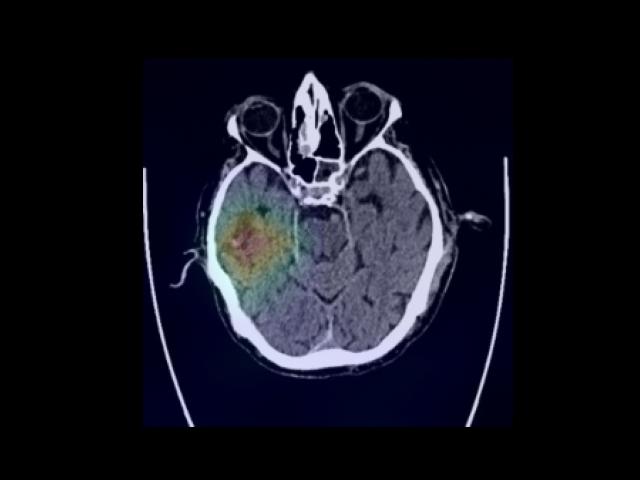

Sample Gallery